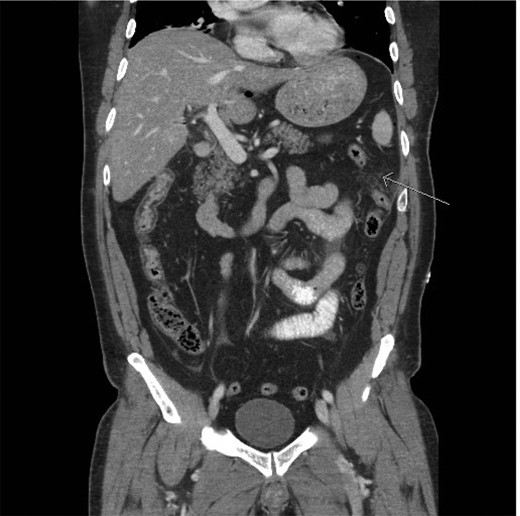

A CT scan demonstrated significant soft tissue stranding/edema of the omentum in the left hemi-abdomen. In addition, there was mild ascites and multiple scattered locules of air (Figs 3–5). No other abnormality of the small or large bowel was identified. He was admitted for observation and broad-spectrum antibiotic therapy was initiated. On post admission day 2, he became diffusely peritonitic, febrile with a temperature of 39.1°C and his oxygen requirements increased to 12 l/min.

CT scan (frontal view) demonstrating multiple locules of air (arrows).

Our case demonstrates the diagnostic dilemma that accompanies delayed bowel injuries. Laboratory tests often give nonspecific results that seldom point to a diagnosis [1]. Imaging studies also fail to establish the etiology. Our CT scan failed to demonstrate significant intraperitoneal free air (Figs 3–5). In addition, oral contrast was utilized, but gross extravasation was not identified.